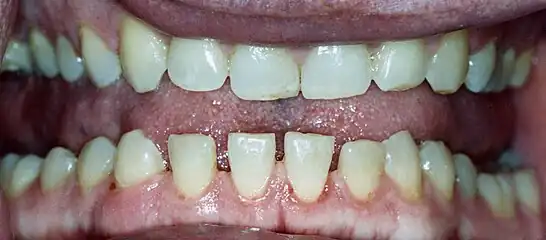

• Pronounced lower jaw protrusion (prognathism) with attendant macroglossia (enlargement of the tongue) and teeth spacing